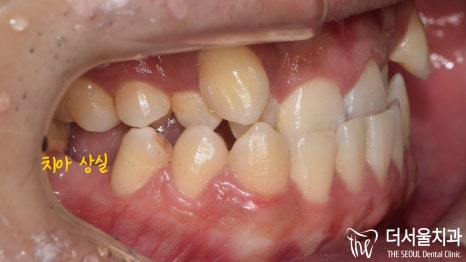

『실제 환자의 사례』

반대로 물리는게 심한 분이군요.

원래대로라면 윗니가 아랫니를 덮고 있어야 되지만,

지금 상황으로는 윗니가 아랫니 뒤쪽으로

쏙! 숨어 있습니다.

이와 더불어 덧니도 함께 관찰되었으며,

삐뚠 치열도 눈에 띄는데요.

교합면에서 관찰해보니,

설측으로 숨어있는 다량의 충치들도

함께 발견되고 있는 상황이였습니다.

주목적은 Class 3을 개선하는거지만,

동시에 총생이나 덧니,

충치치료도 진행해야 겠습니다.

이분의 경우 심한 충치로 인해

아래 어금니가 빠져 있었는데요.

이 공간을 활용하여 아래턱의 후방이동을 유도하고,

추후 임플란트 식립을 진행하는 것으로

최종 계획을 세웠습니다!